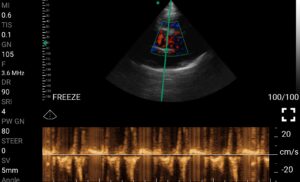

• Doppler καρδιακών βαλβίδων: Βασική εκτίμηση στένωσης/ανεπάρκειας.

• Διαστολική δυσλειτουργία: Εκτίμηση πληρότητας της αριστερής κοιλίας.

Παραδείγματα

Ολες οι παραπάνω απεικονιστικές εξετάσεις έχουν ληφθεί από φορητή συσκευή όπως: Apple Iphone, Tablet, Samsung Mobile Phones και διάφορες άλλες φορητές συσκευές.